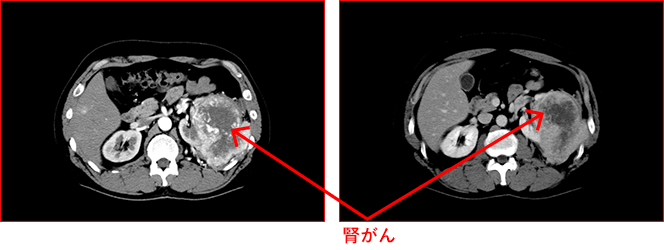

副腎腫瘍はCTではどのように見えますか?

CT スキャンでは、良性の副腎腫瘍または腺腫は、通常、脂肪含有量が高いため、周囲の組織から目立つ、はっきりとした円形または楕円形の病変として現れます。

副腎癌腫としても知られる癌性副腎腫瘍は、大きく不規則な形の塊として現れることがあります。通常、組織の組成が異なるため、密度が不均一で、視認性の低い領域と高い領域があります。

ただし、すべての癌性腫瘍がこのように見えるわけではなく、特定の腫瘍の種類やその他の要因によって外観が異なる場合があります。

癌性腫瘍では、CT スキャン中に血流の増加や造影剤の取り込みの亢進が見られる場合もあります。これは、進行性の腫瘍であることを示唆しています。